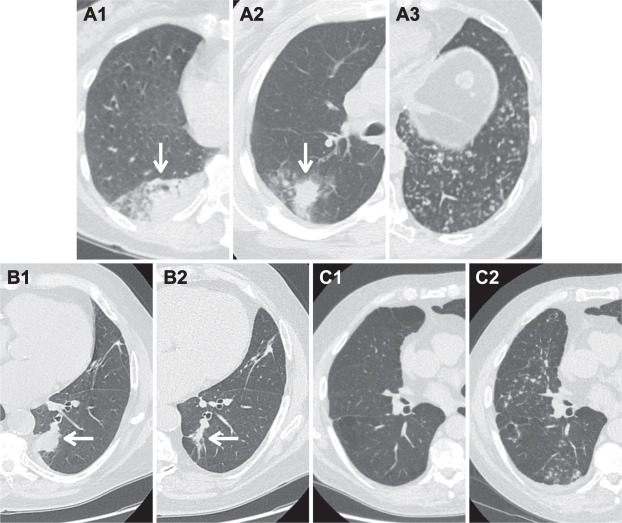

Hình 1. Nang khí thành mỏng. (A) Ví dụ về nang khí thành mỏng đơn giản ở ba bệnh nhân (A1, A2, A3). Nang đơn giản là nang đơn ngăn với độ dày thành < 2 mm (mũi tên) và không được phân loại hoặc quản lý trong Lung-RADS. Cần cẩn thận để tránh nhầm mạch máu (đầu mũi tên) với nốt hoặc thành dày. (B) Ba bệnh nhân mắc bệnh phổi dạng nang khí: lymphangioleiomyomatosis (u cơ trơn bạch mạch – LAM) (B1), bệnh mô bào Langerhans (B2) và viêm phổi kẽ lympho bào (LIP) (B3). Bệnh phổi đa nang (Multicystic lung disease) không được phân loại hoặc quản lý trong Lung-RADS trừ khi nang được xác định có các đặc điểm không điển hình (ví dụ: nhiều ngăn, thành dày, có nốt đi kèm).

Hình 2. Nang khí phổi không điển hình: thành dày. (A) Nang phổi có độ dày thành ≥ 2 mm là “thành dày” (mũi tên) và được phân loại và quản lý trong Lung-RADS v2022. Độ dày thành có thể là chu vi (A1), không đối xứng (A2) hoặc khu trú (A3). Nang thành dày được phân loại là Lung-RADS 4A. (B) Một bệnh nhân 62 tuổi khi sàng lọc CT ban đầu với một nang thành dày (mũi tên, B1)—Lung-RADS 4A. Nốt ổn định sau 3 tháng theo dõi và quay lại sàng lọc hàng năm theo quản lý Lung-RADS v1.1. Khi sàng lọc hàng năm, nang phổi không điển hình đã tăng kích thước với độ dày thành tăng và có nốt mới (mũi tên, B2). Bệnh nhân đã được phẫu thuật cắt bỏ và được chẩn đoán xác nhận là ung thư biểu mô tuyến. Trong Lung-RADS v2022, các nang có thành dày với độ dày thành ngày càng tăng hoặc có dạng nốt thành được phân loại là Lung-RADS 4B.